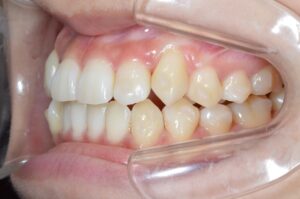

①写真撮影

今の歯並びを色々な角度から撮影します。

せっかくなので矯正前→現在(No.40)で並べてみます。

ぎゅうぎゅうに詰まっていたのが少し緩和されています。